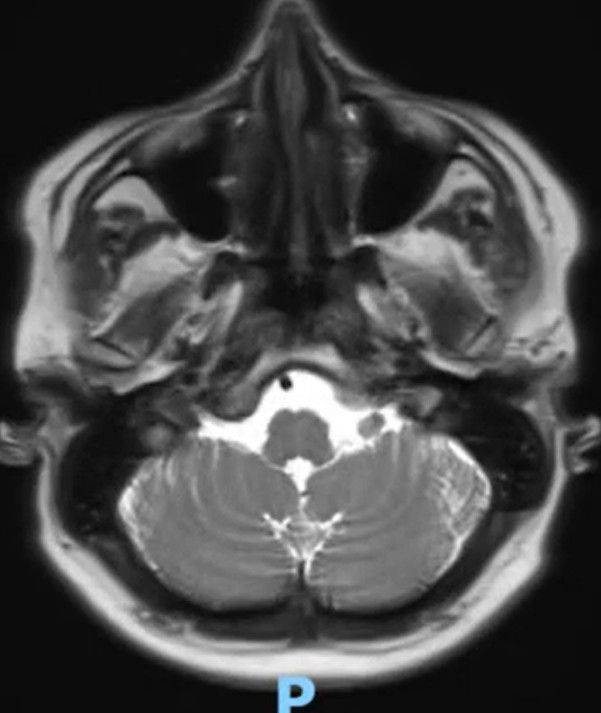

Method: A 37-year-old man with history of controlled Epilepsy who suffered from the subacute onset of cerebellar ataxia and uncontrolled seizures. Abnormalities was found in the cerebellum on initial brain MRI (Fig1,2) and we performed lumbar puncture and other neurological test included infectious, vascular and immunological which were negative. Oligoclonal bands were positive and Cerebral Pet showed cerebellar, frontal hypometabolism and focal hypermetabolism suspect thyroid nodules (Fig 3).

MRI reduction of cerebellum volume in axial T2